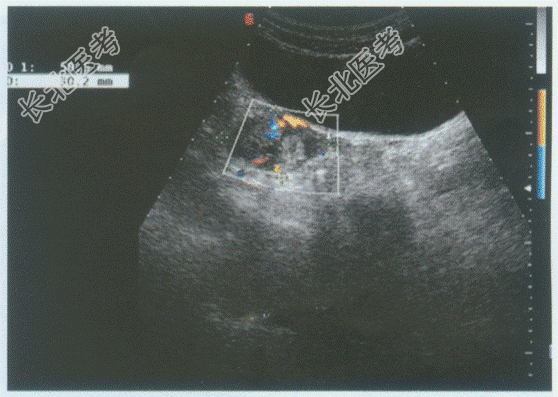

- 单项选择题临床资料:女性患者, 30岁,自诉停经40天, 腹痛伴阴道出血4天。检验:尿妊娠试验阳性。

超声综合描述: 子宫形态大小正常,宫腔内未见胎囊。右卵巢内见无回声, 周边呈环状中强回声,CDFI: 周边可见血流信号。见下图及彩图。

超声提示: A、右卵巢癌

B、右卵巢黄体囊肿

C、右卵巢异位妊娠

D、右卵巢卵泡

E、右卵巢黄素囊肿